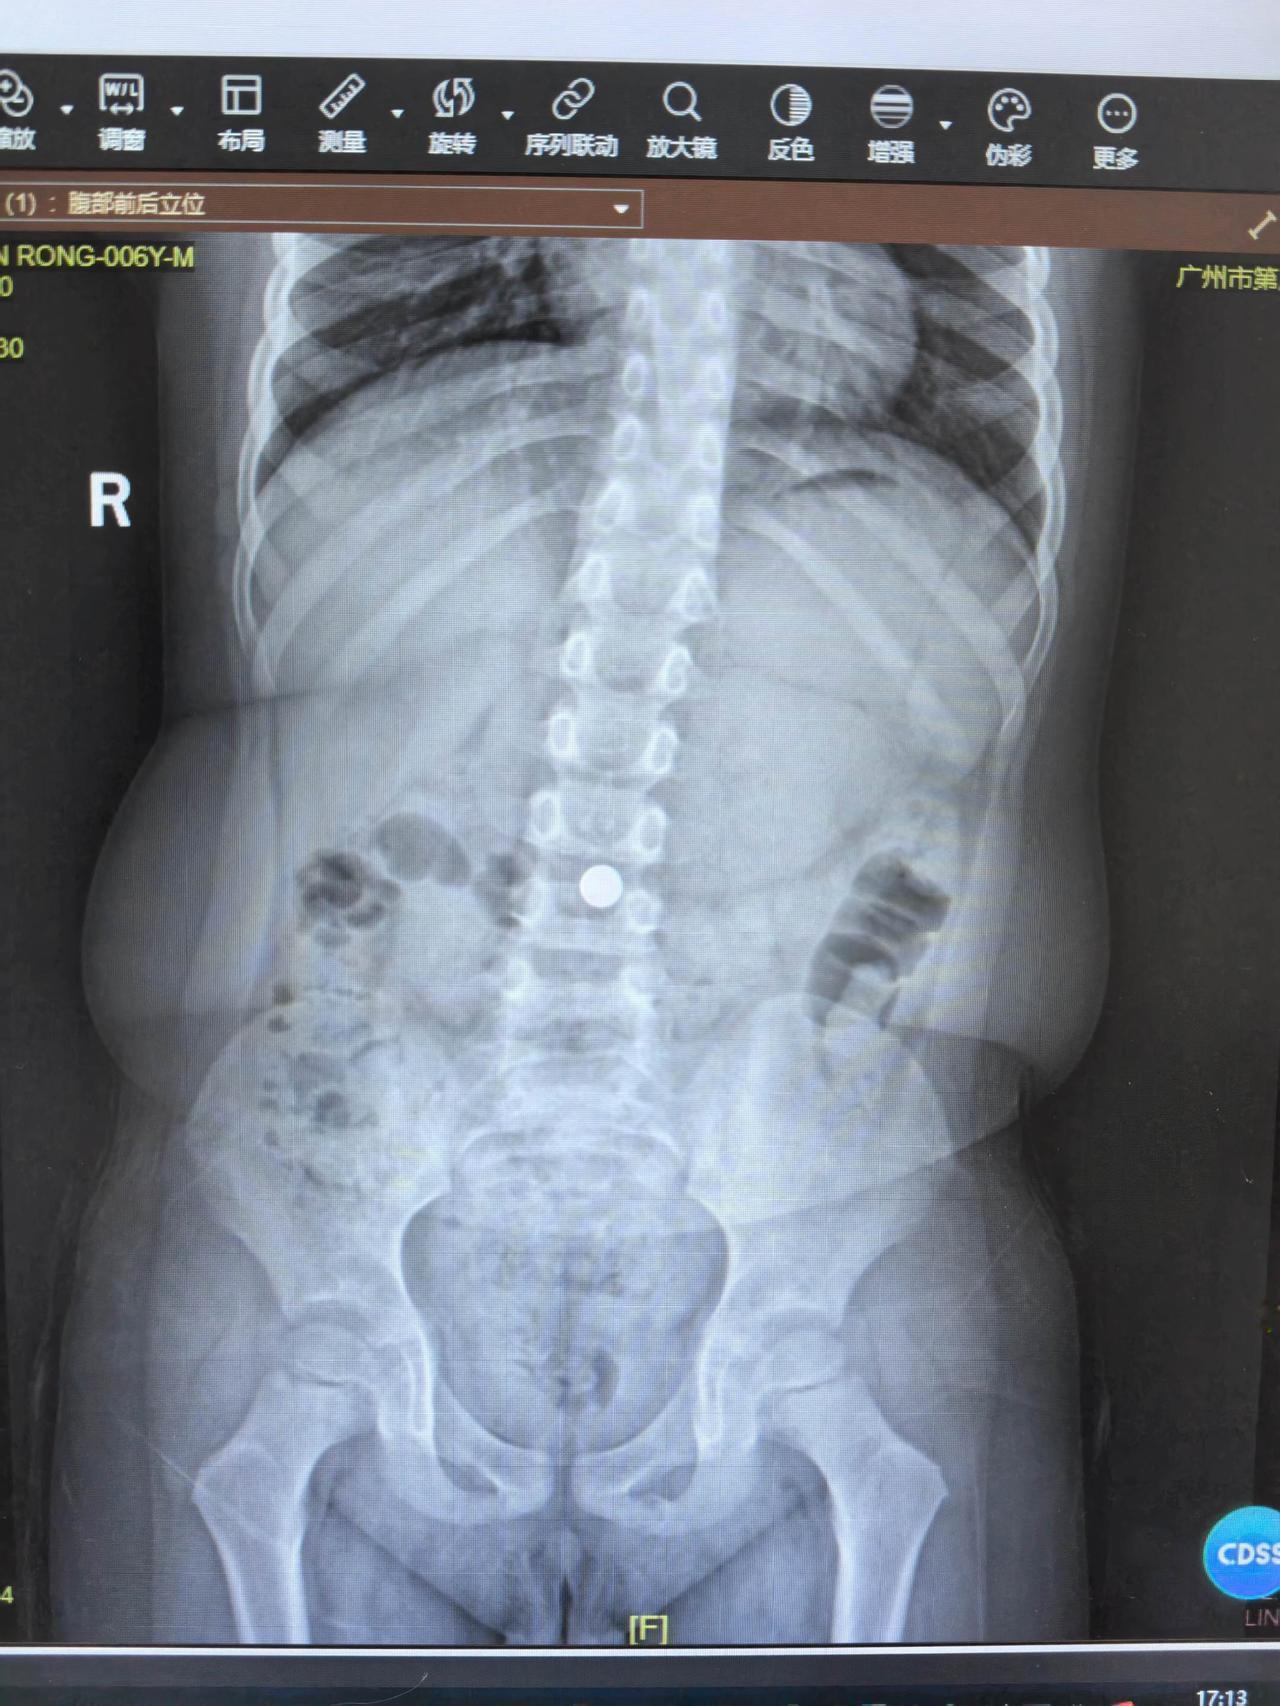

今晚,临下班前,又救了一条命。 一个7岁的女宝,因为经常腹痛,家长认为“肚子有